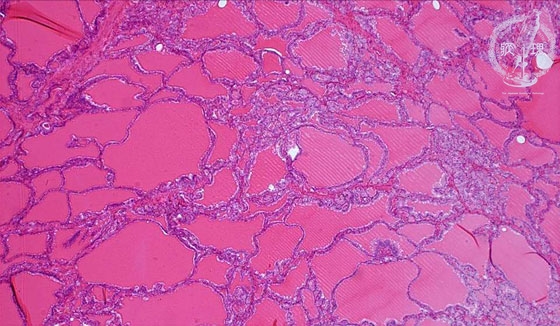

Microscopic findings (HE stain, low power view). Thyroid follicles with various sizes. A Scalloped (“moth-eaten”) appearance is apparent in the edge of the colloid.